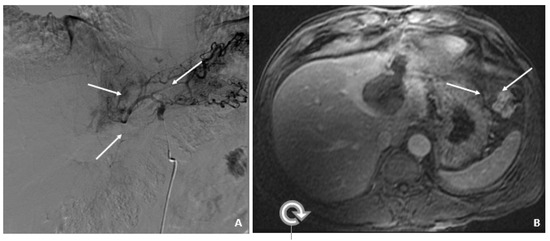

Figure 3.

Recurrent HCC 2 Years Later (April 2011). (A) The contrast-enhanced CT image shows a hyperenhancing lesion in the left lobe (arrows) with adjacent tumor thrombus within the portal vein (dashed arrow). (B) The subsequent axial T1-weighted fat-suppressed postcontrast MRI image shows the lesion (arrows) to a slightly better advantage, along with the portal vein tumor thrombus (dashed arrow). (C) The diffusion-weighted image shows marked hyperintensity (arrow) within the left lobar mass, corresponding to diffusion restriction, typical of malignant tumors.

Subsequent %L3 AFPs remained persistently high with minimally elevated total AFP levels, which indicated recurrent/progressive HCC.